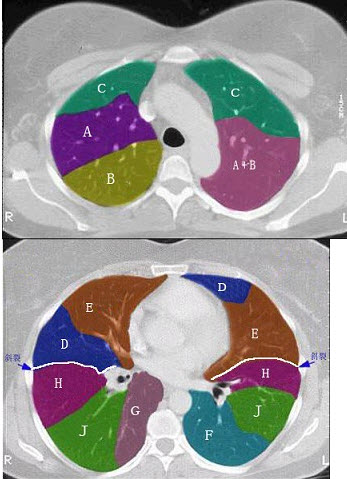

67岁,男,胸痛、咯血、体重下降,请结合CT,检查选出最可能的诊( )

A:肺结核

B:肺上沟瘤

C:错构瘤

D:胸膜间皮瘤

E:神经鞘瘤